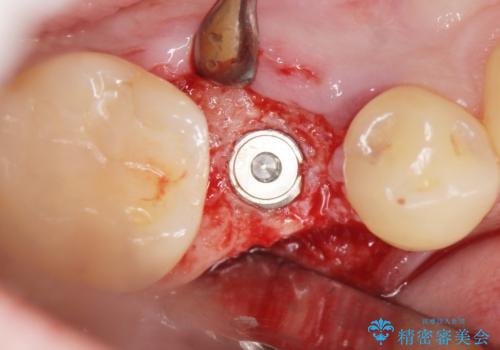

- 奥歯(右下5)のインプラントをご希望し来院された患者様です。

なるべく低予算でとのご希望により、アルファタイトインプラント(保証期間:3年)による治療を行いました。

インプラントの種類:アルファタイト

クラウンの種類:オールセラミッククラウン スタンダード